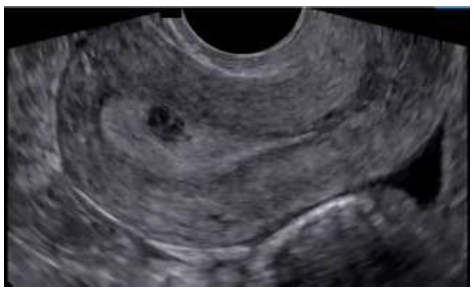

O mioma (leiomioma) uterino é um tumor benigno, muito comum, que pode acometer até 70% das mulheres com 50 anos de idade. Para sistematizar a descrição dos miomas, foi criada a classificação da FIGO (Federação Internacional de Ginecologia e Obstetrícia) juntamente com o grupo MUSA (Morphological Uterus Sonografic Assessment), utilizando estes parâmetros classifique o nódulo abaixo: